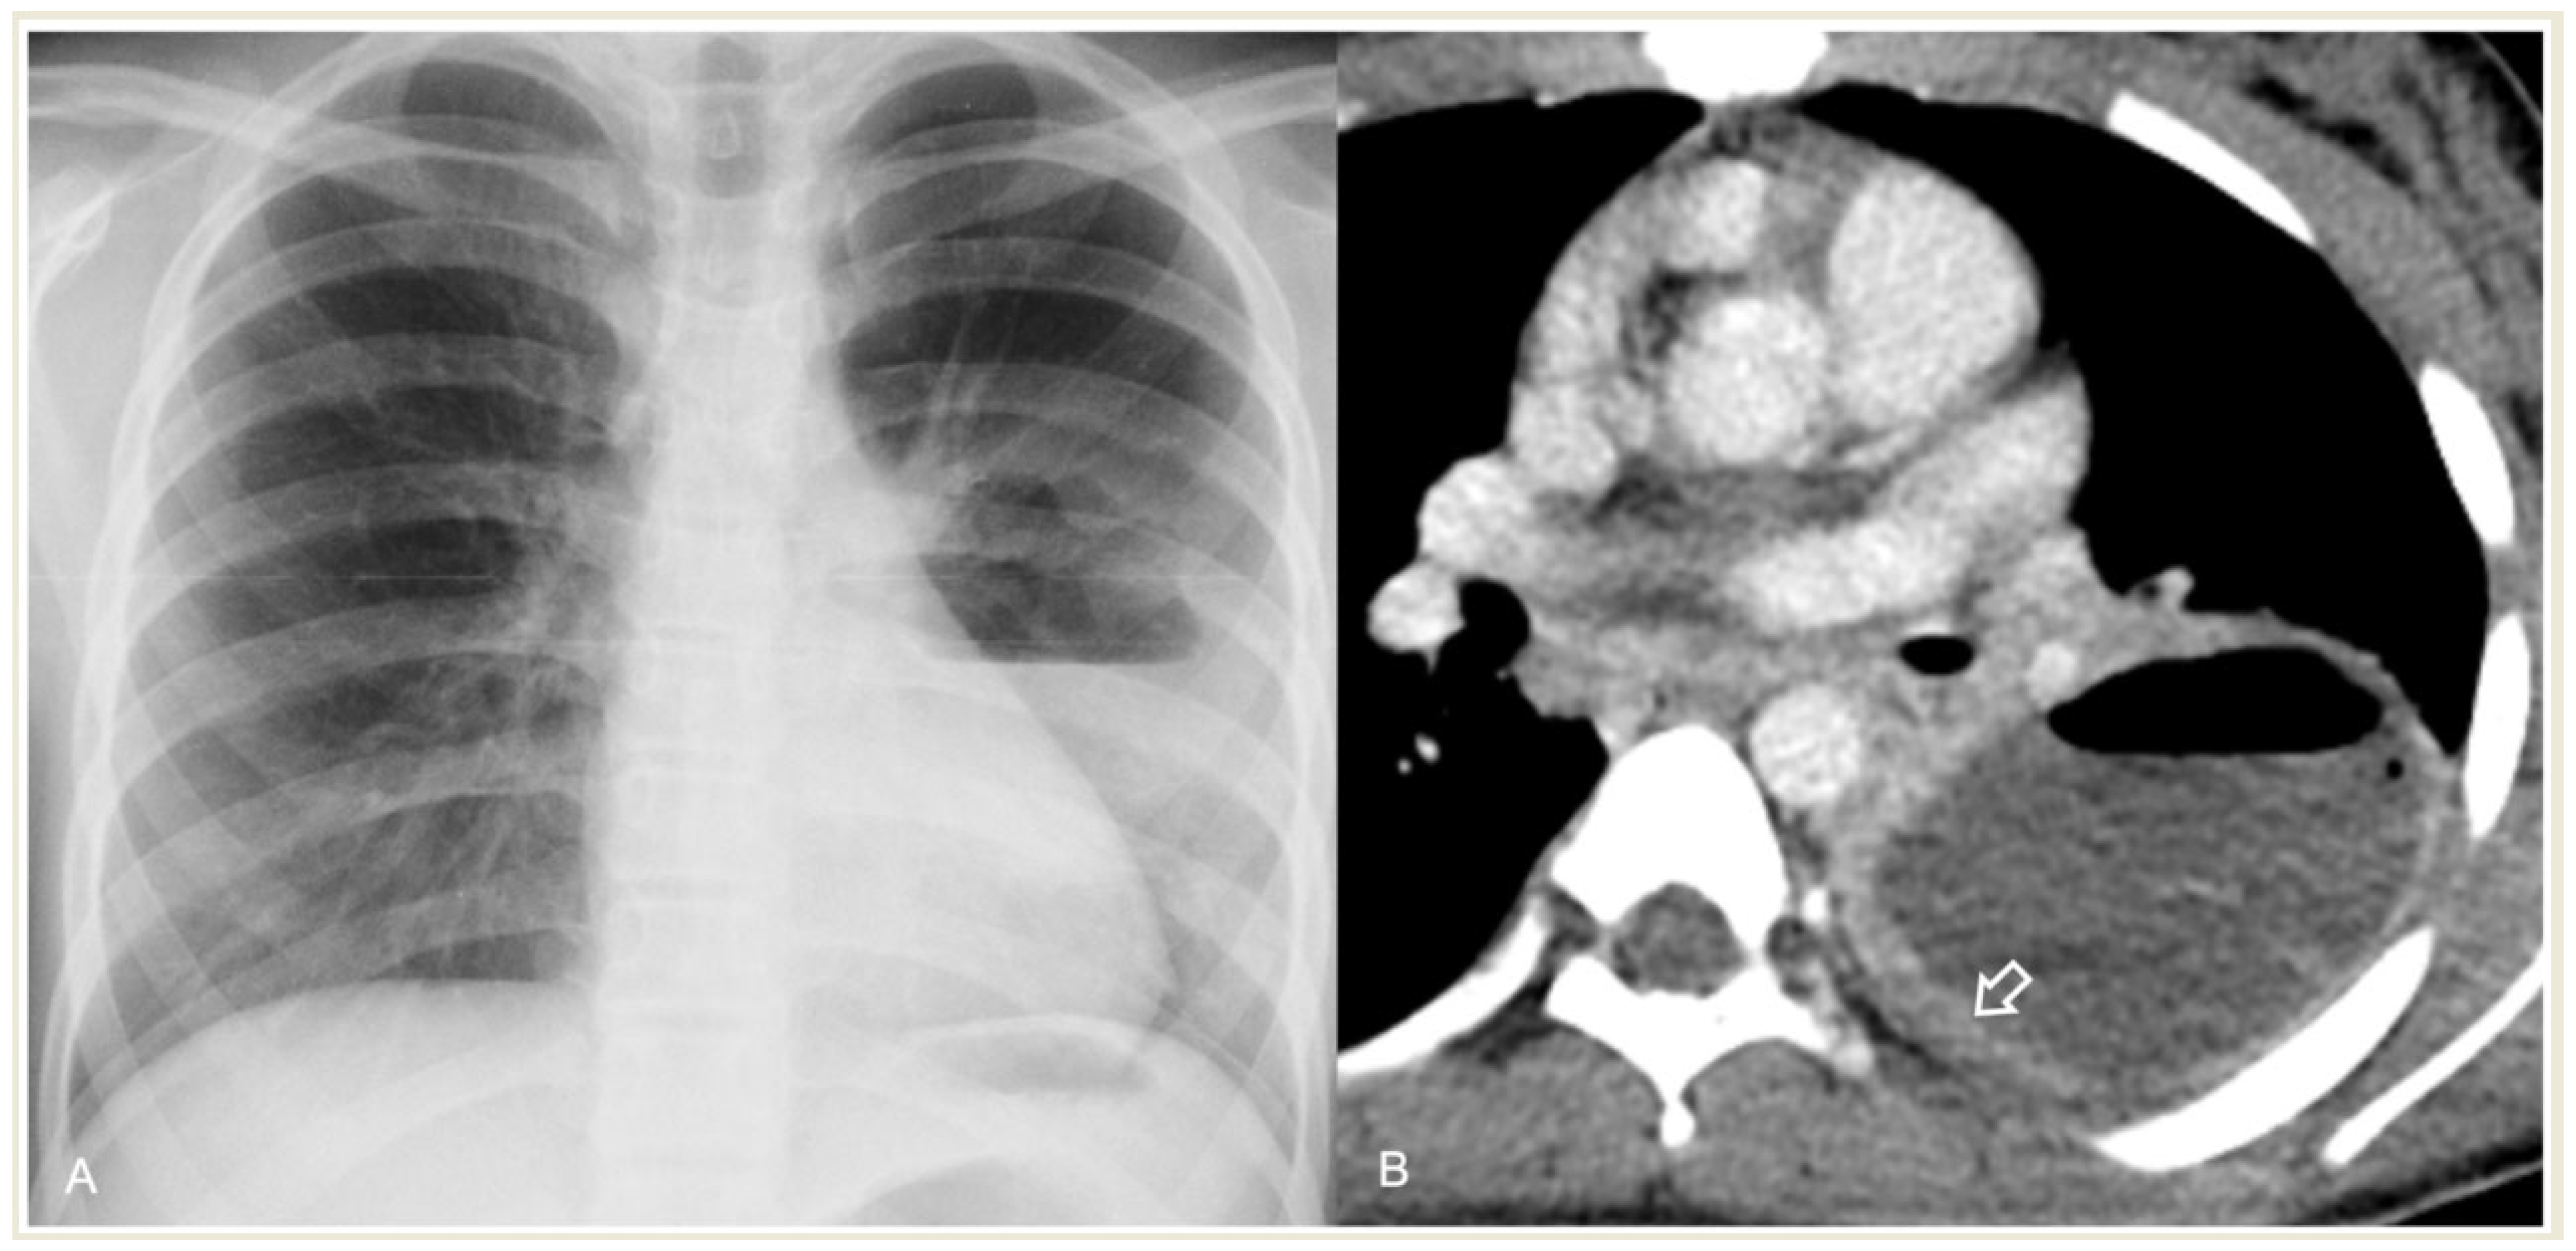

2.4.1. Pleural Effusion—Empyema